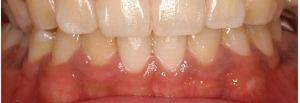

メラニン色素沈着の除去

マイクロスコープとEr:YAGレーザーの併用で、術後の痛みもほとんどありません。